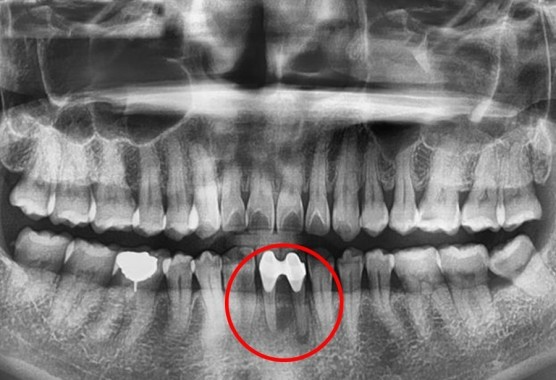

[2020.09.09. 초진 시 구강 상태]

아래 앞니 2개가 이어져있는 브릿지 형태에 뿌리끝 밑 주변 염증이 있는 상태로 내원하셨습니다.

주소는 “욱씬거림과 타치과에서 뿌리까지 썩었다고 했어요.”

환자분들이 오해하기 쉬운 설명이 있었나봅니다.

드러나지 않은 뿌리는 썩지 않는다고 보시면 됩니다.